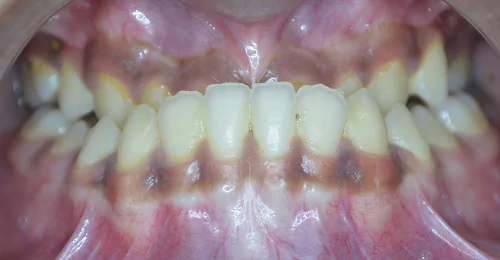

Orthodontic Case – IV

(Case Done by Dr. Sonali Deshmukh M.D.S. / Orthodontist )

Correction of Open Bite

Pre Treatment